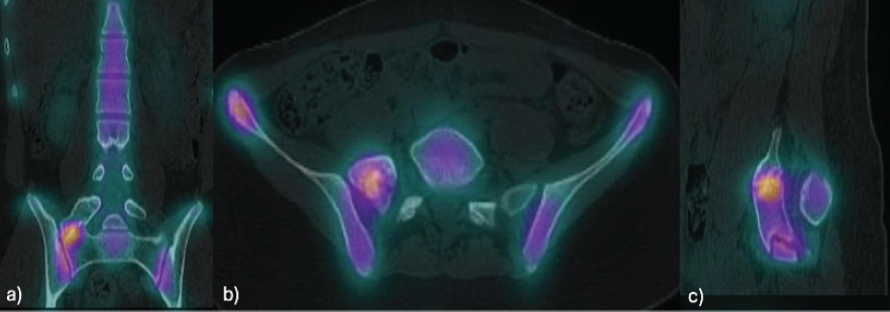

X-rays (Fig. 2), CT scan (Fig. 3), and MRI revealed a LVT with a right hypertrophic transverse process at L5, which articulated with the sacrum and was compatible with Castellvi type IIa. SPECT findings indicated focal hypercaptation within the pseudoarticulation, suggesting symptomatic focus (Fig. 4).

Figure 4: Single-photon emission computed tomography-computed tomography of the lumbosacral region: Focal area of increased uptake at the pseudoarticulation between the right L5 mega-transverse process and the sacrum in the coronal (a), axial (b), and sagittal (c) views.